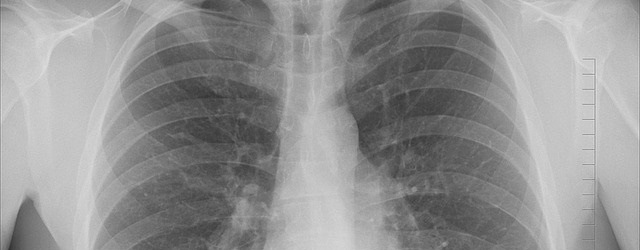

Lungenkrebs - Stadien und Therapiemöglichkeiten

Hier ist der Tumor noch klein und hat noch nicht gestreut. Eine Behandlung ist möglich mittels Laser, z.B. Cyberknife und/oder Protonenbestrahlung, Hormone und Chemotherapie. Die Prognosen sind sehr gut, auch eine operative Entfernung ist möglich, man kann mit einem Lungenlappen leben. Das geht aber nur, wenn nur 1 Lungenlappen befallen ist. Lungenkrebs erzeugt keine Schmerzen, daher ist die Erkennung oft nur ein Zufall oder wenn Symptome auftreten erst im Endstadium. Eine Lungenaufnahme bei Risikopatienten zur frühzeitigen Erkennung ist daher sinnvoll. Das Wachstum kann unterschiedlich schnell gehen, woran liegt das?